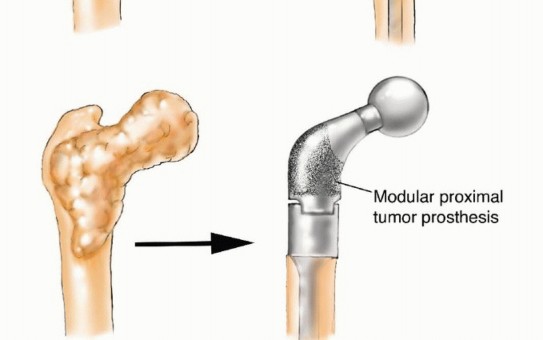

قد يحتاج المرضى المصابون بـ MBD إلى تدخل جراحي لإدارة كسر مرضي وشيك أو موجود بالفعل، أو لتخفيف الألم الشديد المرتبط بآفة متقدمة محليًا لم تستجب للعلاجات الأخرى. هذه "الأزمات الهيكلية" تؤدي إلى فقدان كبير في الوظيفة، وألم، وتدهور في جودة الحياة. في حالات نادرة، قد تُجرى الجراحة لإزالة ورم نقيلي عظمي وحيد بهدف تحسين البقاء على قيد الحياة على المدى الطويل لمرضى مختارين. ومع ذلك، فإن معظم التدخلات الجراحية تكون تلطيفية في المقام الأول، وتهدف إلى التحكم الموضعي في الورم، وتوفير الاستقرار الهيكلي للموقع المعالج جراحيًا، واستعادة الوظيفة الطبيعية بأسرع وقت ممكن.

يُعد الفشل في تحقيق هذه الأهداف أمرًا شائعًا، حيث تصل معدلات الفشل في جراحات MBD إلى 40%، وغالبًا ما تنتج عن تثبيت أولي ضعيف، أو اختيار غير مناسب للزرعات، أو تقدم المرض في مجال الجراحة. إن محاولة علاج كسر مرضي كما لو كان كسرًا ناتجًا عن صدمة ستفشل في معظم الحالات لأن المرض الأساسي يعيق عملية التئام الكسر الطبيعية.